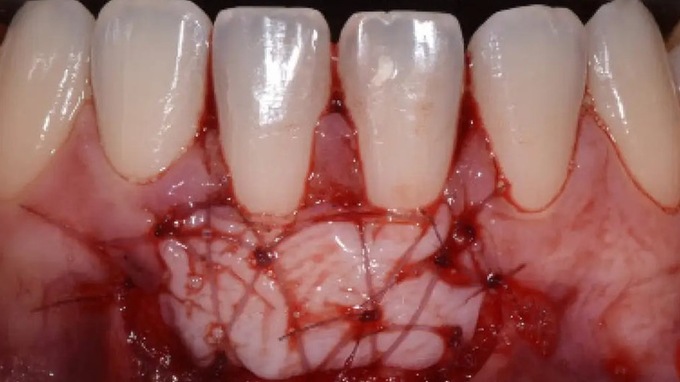

- Les tracés d’incision et les sutures

- Les chirurgies parodontales d’assainissement

- Indication et description des différents lambeaux d’assainissement

- Incisions et sutures

- Lambeaux d’assainissement

- Greffe épithélio-conjonctive

- Greffe conjonctive en tunnel